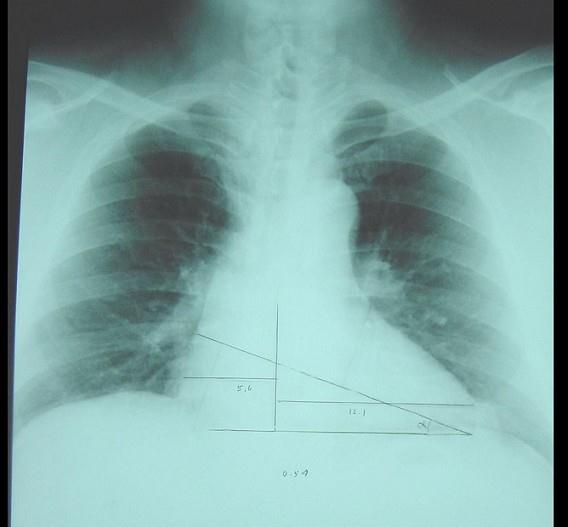

此心脏正位片描述正确的是 ( )A、“普大型”心脏B、“二尖瓣型”心脏C、“中间型”心脏D、“横位型”心脏E、“主动脉瓣型”心脏

问题 此心脏正位片描述正确的是 ( )

选项 A、“普大型”心脏 B、“二尖瓣型”心脏 C、“中间型”心脏 D、“横位型”心脏 E、“主动脉瓣型”心脏

答案 D